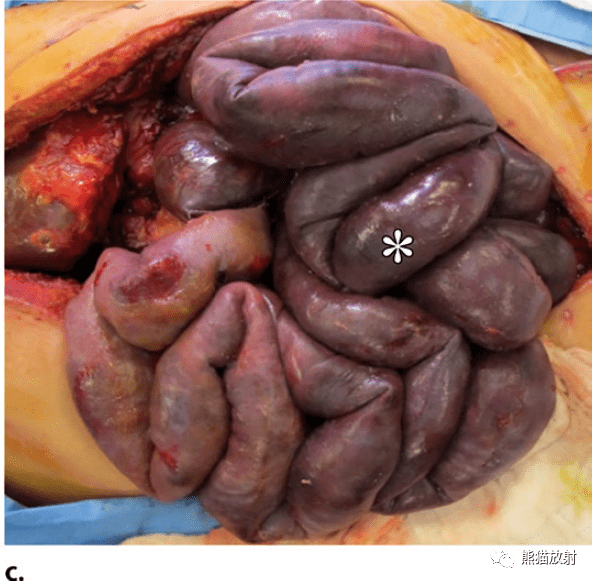

肠子都黑了 8岁男童腹痛一天竟是这种罕见病!医生: 于无形